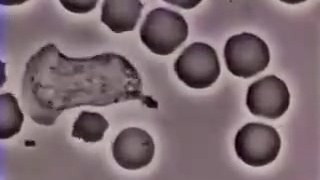

πΏΠΠ΅ΠΉΠΊΠΎΡΠΈΡ Π³ΠΎΠ½ΠΈΡΡΡ Π·Π° Π²ΠΈΡΡΡΠΎΠΌ